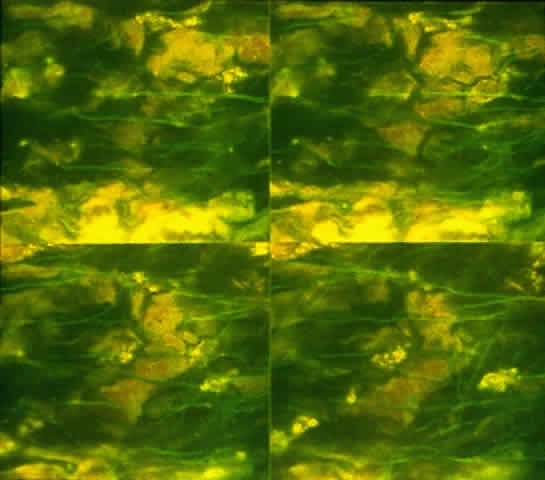

Ultrastructural studies of goblet cells suggest an apocrine secretory mechanism that releases mucus in the form of packets; however, this has not been demonstrated conclusively (Fig. 14A and B).50 This secreted mucus forms the posterior layer of the tear film. Other layers of the tear film include an aqueous layer containing soluble proteins and mucins and a thin anterior layer consisting of meibomian gland oil.51 Mucus is released rapidly in response to surface irritants, trauma, or toxins. This reflexive response is necessary to replenish the mucous layer and to protect the ocular surface. Recent evidence indicates that parasympathetic and sympathetic nerves are located adjacent to the goblet cells. It is not clear whether the cells are directly innervated (Figs. 15 and 16).52,53 However, corneal debridement causes goblet cell secretion,54 suggesting that ocular damage stimulates the reflex sensory nerves of the cornea to activate a local reflex arc. In turn, the efferent neurons in the conjunctiva activate and release neurotransmitters, which stimulate the goblet cells. This is supported by the fact that topical application of vasoactive intestinal peptide (VIP), serotonin, epinephrine, dopamine, or phenylephrine stimulates conjunctival goblet cell mucus secretions.52,54

Fig. 15. Immunolocalization of vasoactive intestinal peptide in conjunctival flat mount. Fluorescence micrographs are a montage of sections imaged parallel to the conjunctival surface at 1-μm intervals with a confocal microscope. Vasoactive intestinal peptide-containing nerves appear as green lines.

Fig. 16. Fluorescence micrograph of section from inferior conjunctiva showing tyrosine hydroxylase (TH)-containing nerve fibers. Presence of TH indicates that sympathetic nerve fibers surround individual goblet cells. (Original magnification; × 600. Dartt DA, McCarthy DM, Mercer HJ et al: Localization of nerves adjacent to goblet cells in rat conjunctiva. Curr Eye Res 14:993, 1995)